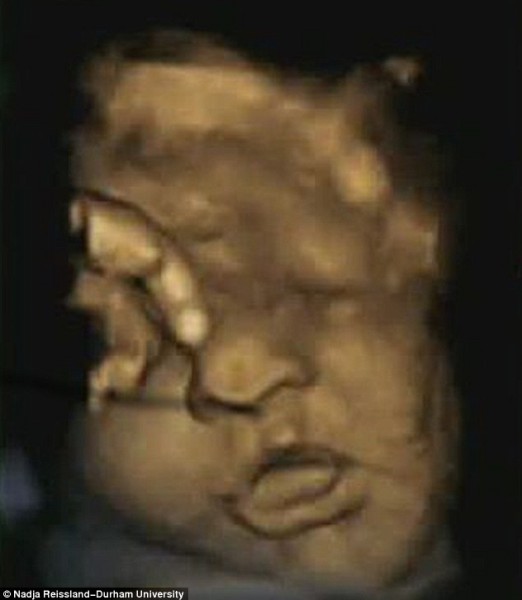

كشف فريق من العلماء والباحثين بجامعة درهام البريطانية عن مفاجأة كبيرة هى الأولى من نوعها على الإطلاق، حيث أشاروا أن الجنين يتمرن على الابتسامة داخل رحم أمه استعداداً للقاء أبويه، وذلك حسبما أظهرت مجموعة من الصور رباعية الأبعاد “4D”، والتى سلطت الضوء على تعبيرات وجوه مجموعة الأجنة قبل حدوث الولادة بفترات تصل إلى 16 أسبوعا.

يذكر أنه تم التقاط هذه الصور رباعية الأبعاد باستخدام أشعة الموجات فوق الصوتية لحوالى 15 جنينا، تتراوح أعمارهم ما بين 24 إلى 36 أسبوعاً من بداية الحمل.